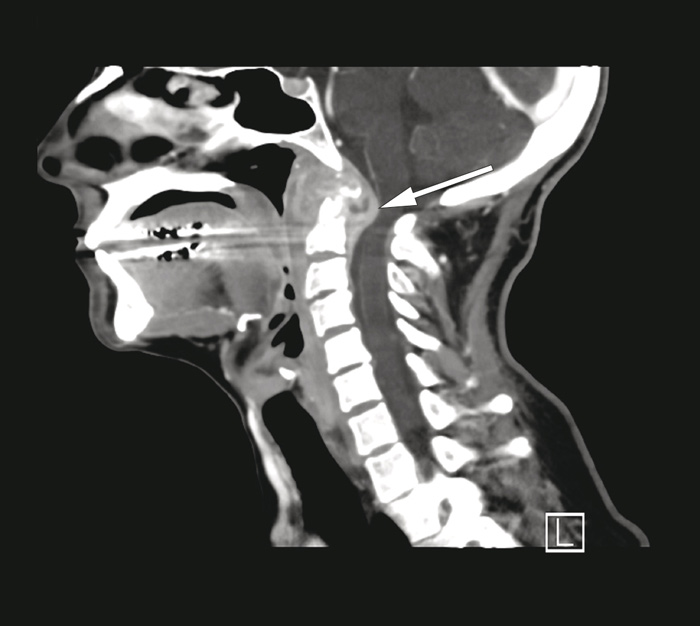

Hun ble innlagt for medisinsk utredning på grunn av langvarig og uavklart, antatt alvorlig tilstand. Ved innleggelsen hadde hun svelgevansker og redusert matlyst. Hun var i god allmenntilstand og afebril. Man fant ved øre-nese-hals-undersøkelse en neseseptumperforasjon, men ellers normale funn. C-reaktivt protein (CRP) var 85 mg/l (< 5 mg/l). Blodkulturer viste ingen oppvekst. Som ledd i utredningen, og på grunn av hennes nevrologiske symptomer, ble det dagen etter innleggelsen rekvirert CT av collum og thorax samt MR av collum. Disse undersøkelsene viste destruksjon av atlasbuene og dens axis, med betydelig omkringliggende bløtdelshevelse og innsnevring av spinalkanalen med kompresjon av medulla (fig 1).

Funn ved CT- og MR-undersøkelsene kunne være forenlig med ondartet sykdom, uttalt artritt eller lokalisert infeksjon. Destruksjon av øvre cervikalcolumna ville kunne gi en ustabil nakke med risiko for økende nevrologiske symptomer.